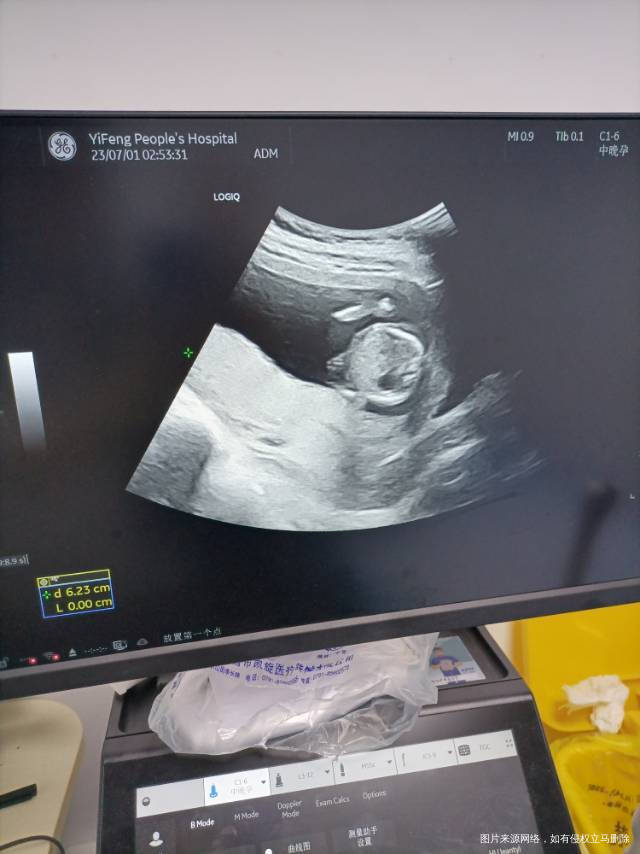

医生我刚好16周 凌晨有水样褐色分泌物流出来挺多的,就去急诊医生要求住院保胎,说我胎盘前置,覆盖宫颈口很危险,目前就打了间苯三酚跟黄体酮 要紧吗?我这个是试管的宝宝 来之不易 真的很担心 现在一天都有褐色分泌物 后面能长上去吗

你目前的情况是胎盘堵着宫颈口,这样的情况不能剧烈活动,不能同房,不能多走路,现在没有办法让它长上去,只能顺其自然,在医院里保胎尽量的少活动就可以的,一周后复查看看吧

目前只有褐色分泌物,说明出血不多,注意休息,继续用药,黄体酮,保胎丸,止血药及间苯三酚治疗,后期也有长上去的,不要担心,注意不同房,不大便干结,不剧烈运动,祝顺孕!

后面能不能涨上去不好说,人为也没办法干预,多数人都能涨上去。用上保胎药,多休息,不能剧烈活动,不能同房,希望孕期顺利